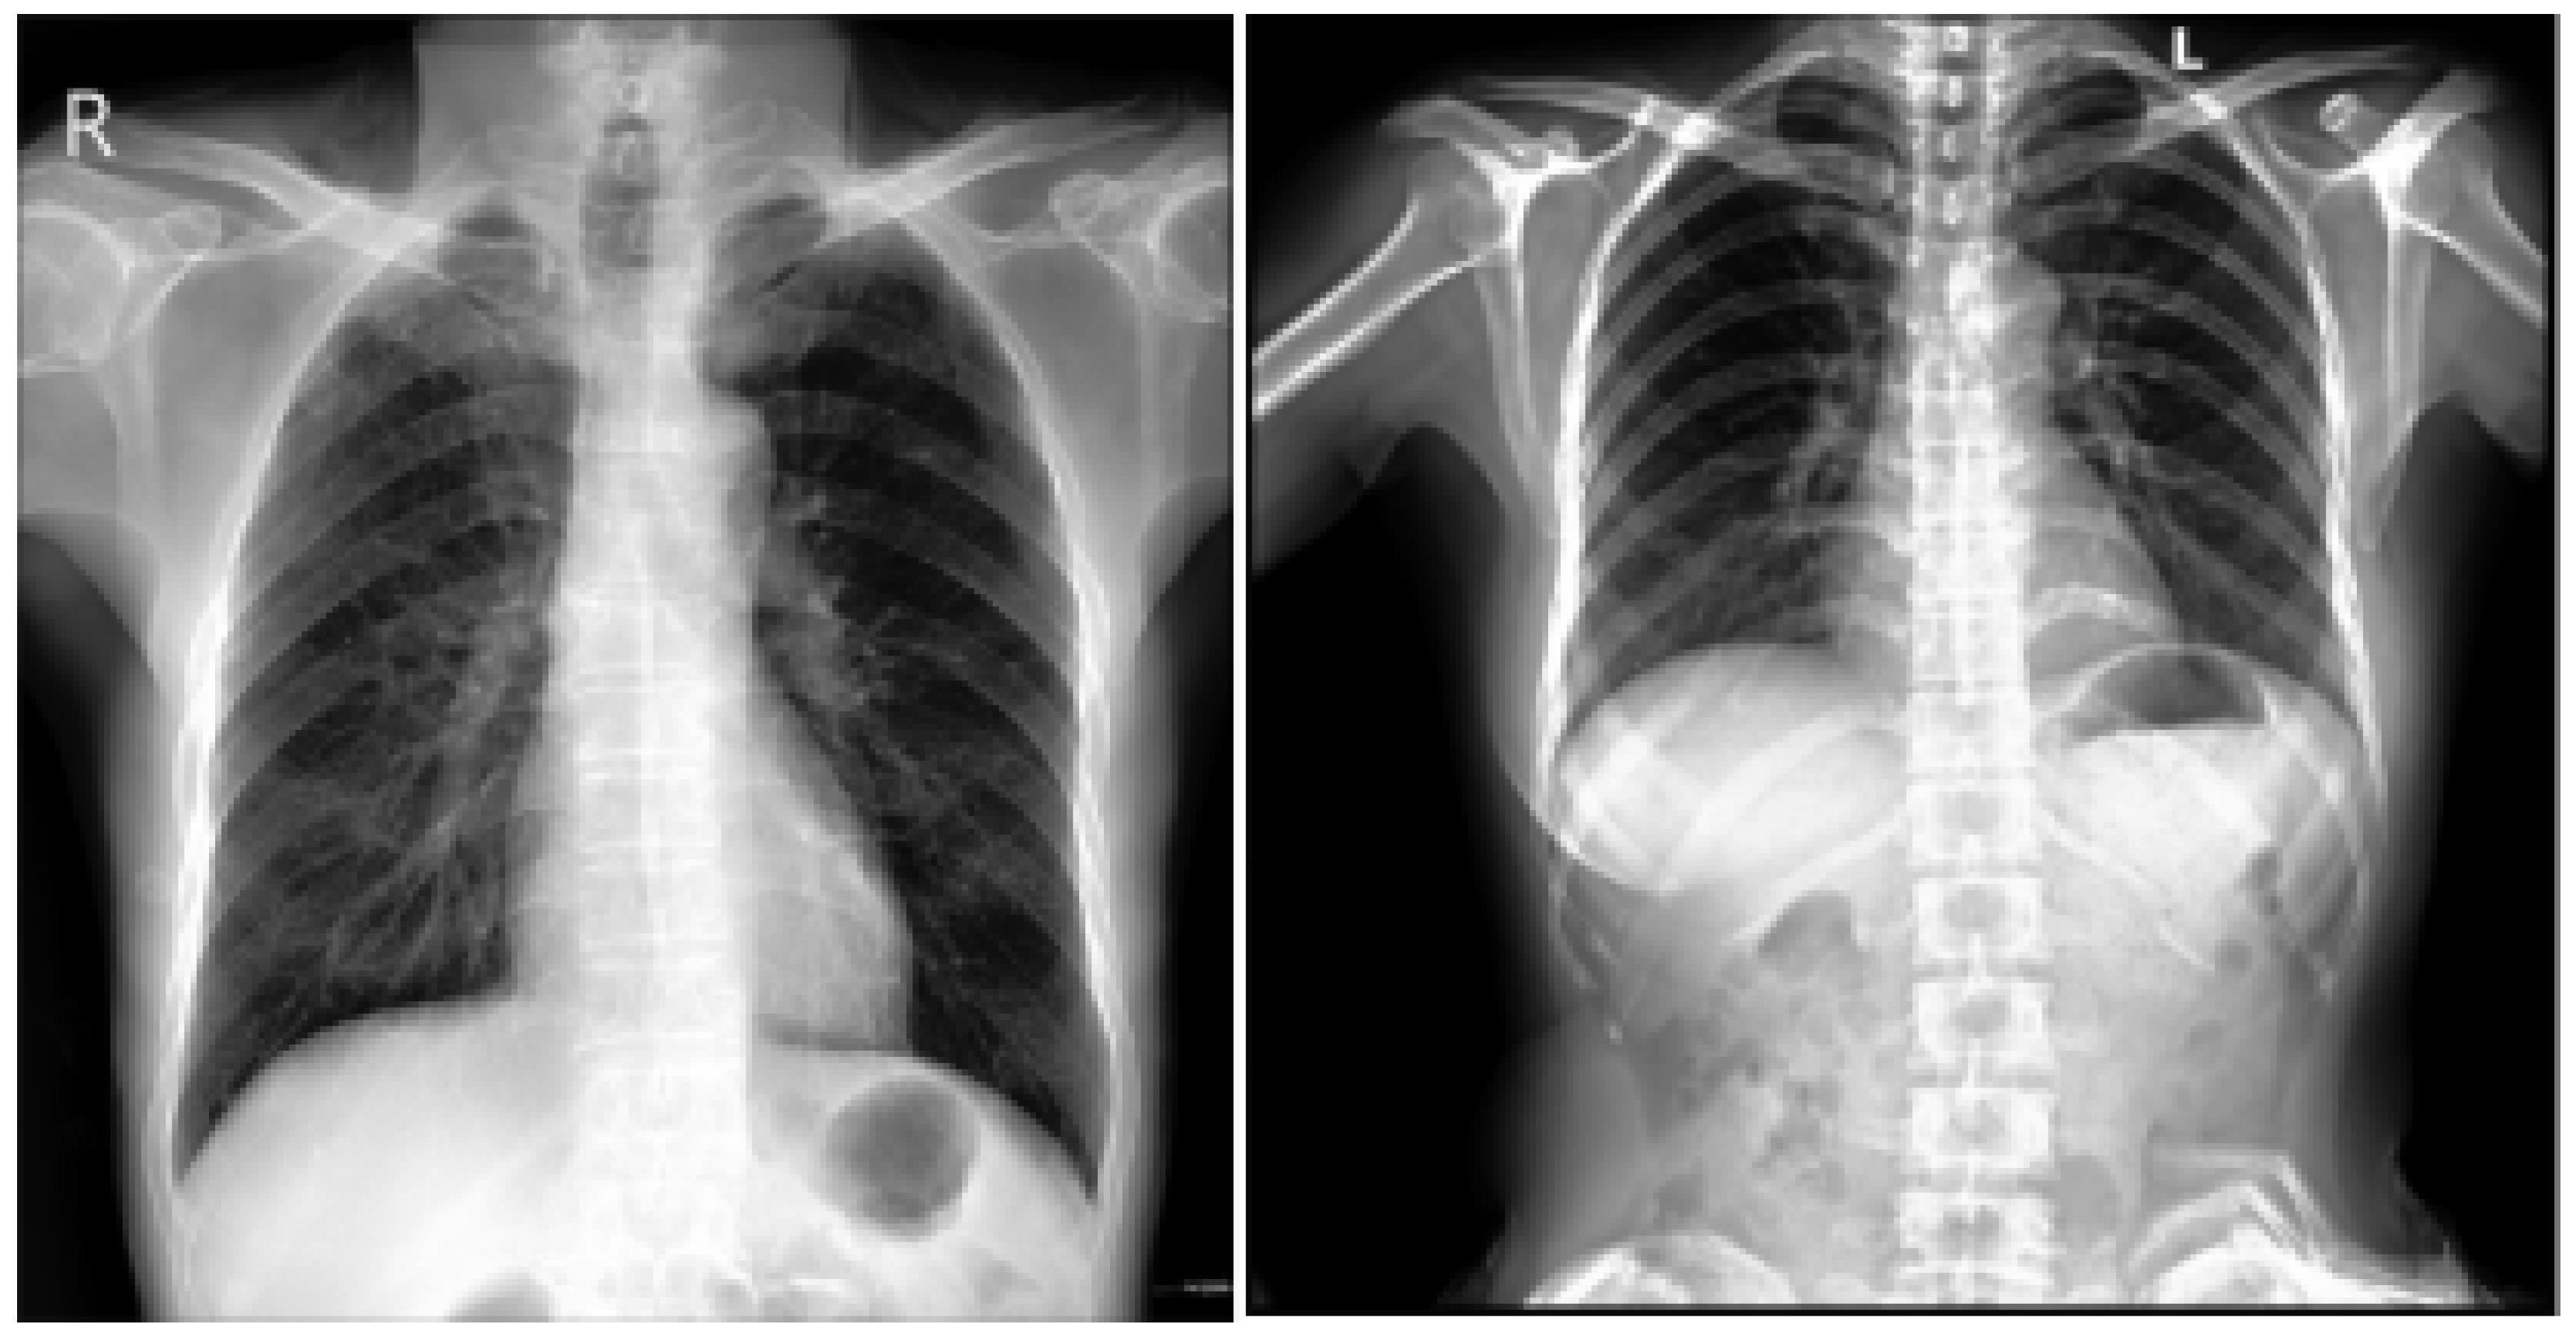

3.1.1. CXR NIH Dataset

The dataset comprises 112,120 X-ray images with disease labels from 30,805 unique patients [21]. The samples from the CXR NIH dataset are shown in Figure 3. Disease labels were extracted from radiology reports using NLP, achieving over 90% accuracy and supporting weakly supervised learning.

Figure 3.

CXR NIH dataset samples [21].

In order to gain a representative insight into the subject matter, the study utilized the CXR NIH dataset. This is a large-scale hospital-grade database comprising 108,948 frontal-view CXR images from 32,717 patients, and it has gained recognition as a valuable resource within the field [22]. The dataset includes images labeled for eight common thoracic diseases using an NLP system applied to radiology reports. While this automated approach enables scalable and consistent labeling with over 90% estimated accuracy, it may occasionally produce ambiguous or incorrect labels.

This study focused on two subsets of the dataset: images labeled as cardiomegaly and normal. This approach enabled the evaluation of model performance in distinguishing normal from pathological cases. Despite its limitations, the NIH CXR dataset remains a valuable resource for thoracic imaging research.

3.1.3. CXR VinDr Dataset

This was developed to provide the research community with a large-scale, high-quality collection of CXR images annotated with detailed and reliable labels [26]. The samples from the CXR VinDr dataset are shown in Figure 5. This dataset was constructed using over 100,000 raw images in DICOM format, which were retrospectively collected from two of Vietnam’s largest and most prominent hospitals: Hospital 108 and Hanoi Medical University Hospital [27]. These facilities contributed to the dataset’s diversity and representativeness by including many cases and patient demographics.

Figure 5.

VinDr-CXR Dataset samples [26].

From this initial pool, a carefully curated subset of 18,000 posteroanterior (PA) view CXR scans were selected for publication. These scans are of particular value as they facilitate the visualization of critical radiological results and the categorization of common thoracic diseases. This provides researchers with a robust dataset that can be used for several applications, including disease detection and model validation.

3.1.4. PadChest Dataset

This is a comprehensive and valuable resource for medical imaging research, consisting of over 160,000 CXR images obtained from 67,000 patients [28,29]. The samples from the PadChest dataset are shown in Figure 6. These images were collected between 2009 and 2017 at San Juan Hospital in Spain, representing various cases and clinical scenarios [30]. The dataset includes images captured in six position views, providing versatility for various radiological studies. Additionally, it contains extensive metadata detailing information about image acquisition techniques and patient demographic characteristics, further enhancing its utility for diverse research applications.

Figure 6.

PadChest dataset samples [28].